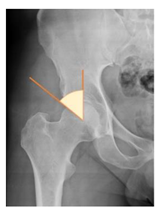

Plain radiographs were evaluated preoperatively and at the most recent follow-up, after appropriate calibration. Positional parameters were assessed according to values guidelines from published literature, as listed in Table 1 [23,24,25,26,27,28,29,30,31]. Femoral stem and acetabular cup osteointegration were quantified according to Engh [32] and Moore scale [33]. Heterotopic ossifications were graded according to the Brooker system [34].

3.4. Radiographic Evaluation

Preoperative and postoperative radiographic data are reported in Table 4. Preoperatively, 18 THR (24.3%) were implanted in skeletally immature children with closed triradiate cartilage (1 ≤ Risser ≤ 3). Radiographic acetabular insufficiency (LCEA < 25° and AI > 13°) was detected in 14 hips (18.9%), while protrusion was present in 3 hips (4.1%) An excessive valgus of the femoral neck was observed in 19 hips (25.7%), while an important varus deformity was present in 7 hips (9.5%).

Postoperative radiographs showed a significant vertical malposition of the cup in 1 case (1.4%), a significant varus stem in 8 cases (10.8%) and a significant valgus stem in 1 case (1.4%). Two patients (2.7%) showed moderate heterotopic bone formation (Brooker ≥ 2), that did not significantly affect the hip motion and symptoms. All those THR that did not undergo revision showed good radiographic osteointegration, with no evidence of implant breakage, radiographic lucencies, bone defects, cup migration, or stem subsidence at the most recent radiographs.